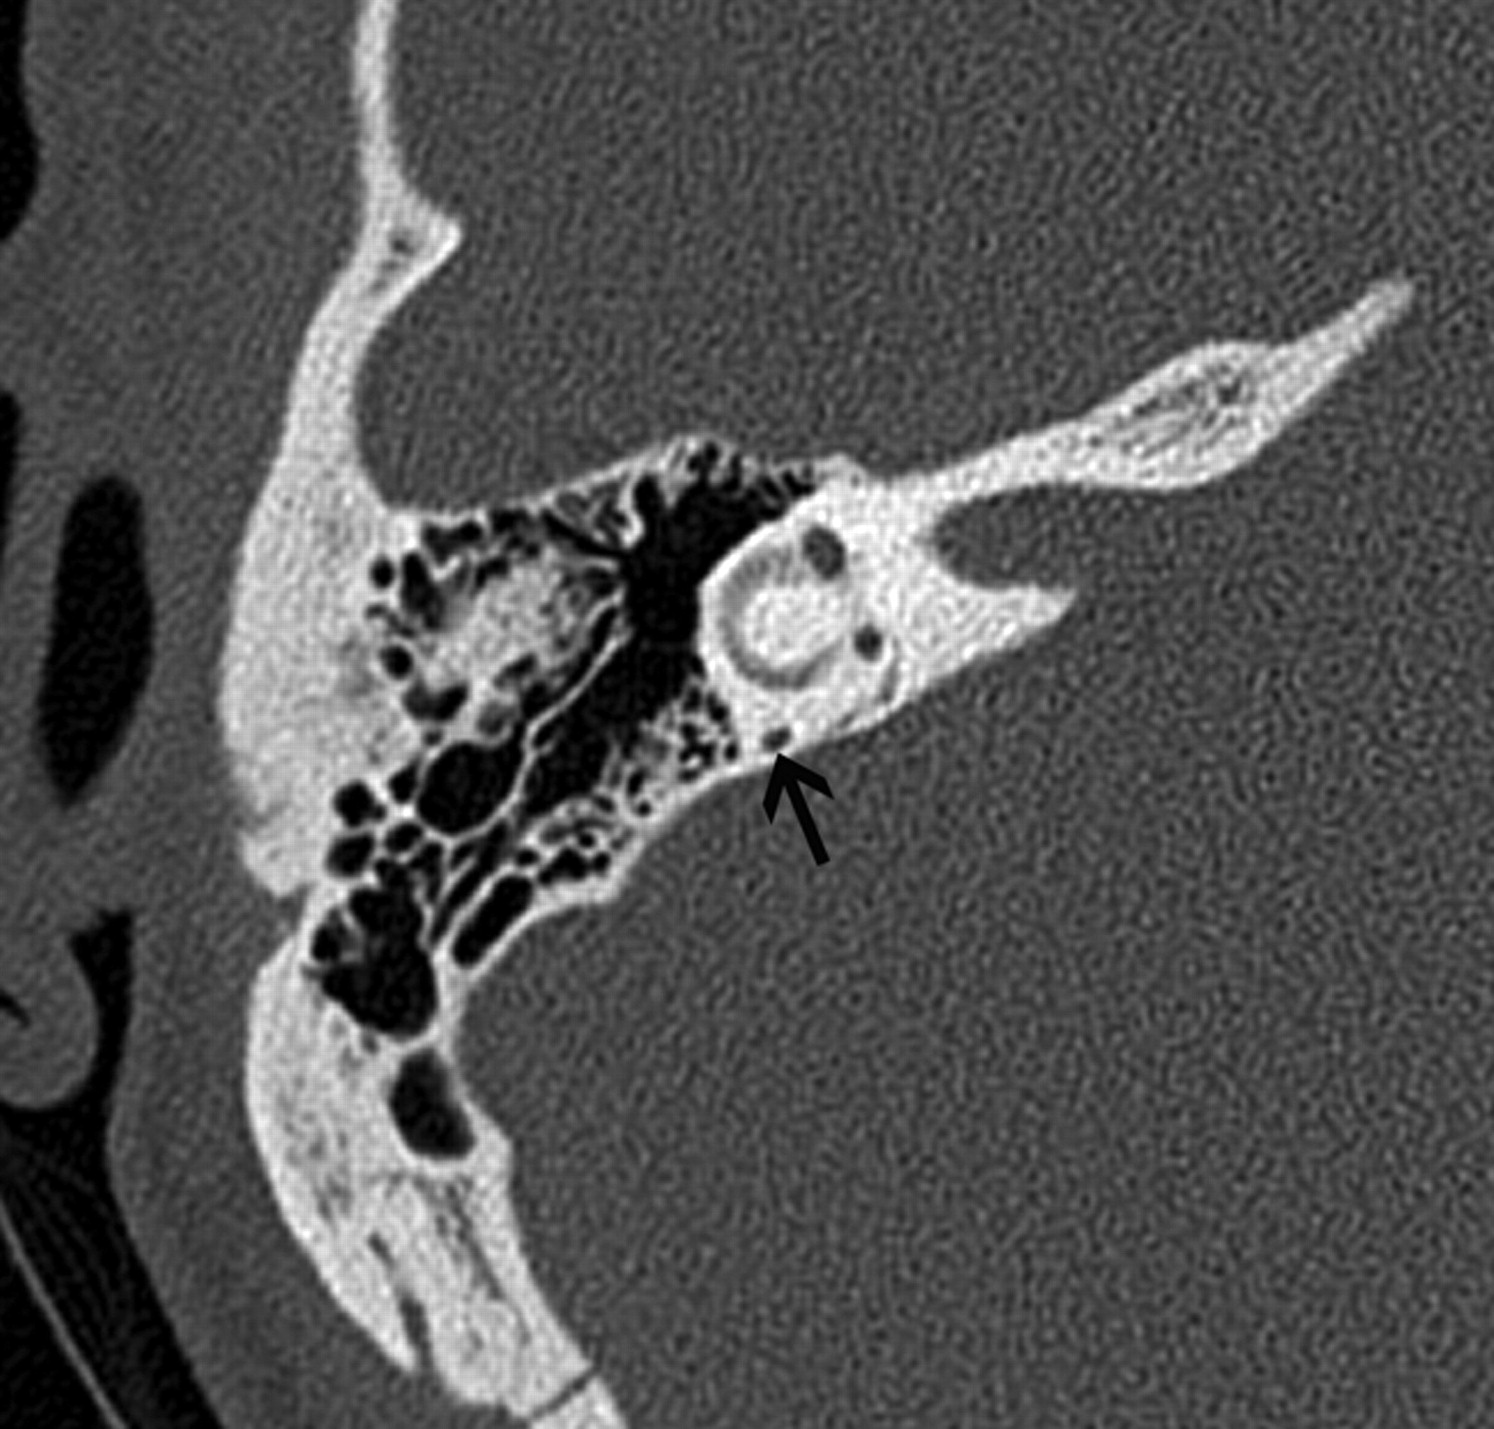

On axial CT images, an aberrant ICA is seen as a tubular structure running horizontally through the middle ear from posterior to anterior (Fig 2A). The inferior tympanic canaliculus is enlarged, and the vertical segment of the petrous ICA is absent. The aberrant ICA is often smaller than the contralateral normal ICA19 and may be difficult to detect on conventional MR imaging. On MR angiography, the aberrant ICA extends more laterally than its normal course. This has been termed the 7 or reversed-7 sign (Fig 2B).20

Aberrant course of the ICA in a 25-year-old man presenting with pulsatile tinnitus. A, Enhanced axial CT image demonstrates an abnormal lateral course of the right ICA through the middle ear (white arrow). Also note dehiscence of the overlying bony plate. B, Anteroposterior projection image from the MR angiogram of the same patient demonstrates decreased caliber and lateral deviation of the aberrant ICA on the “right reversed-7 sign” (black arrow).